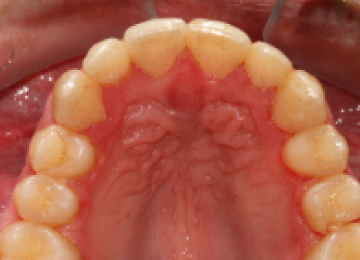

Брекеты: фото До и После